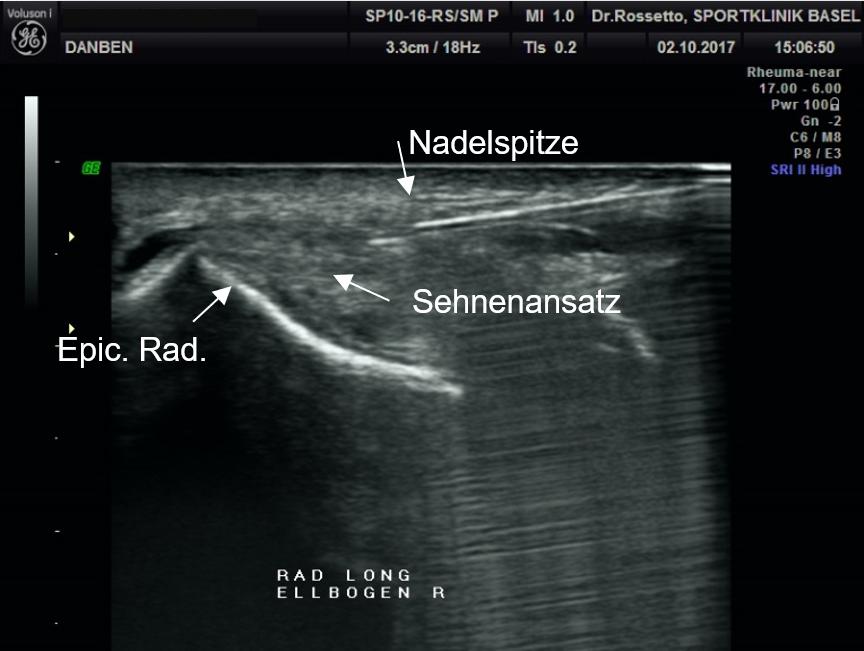

Ultraschall gesteuerte Injektion von ACP bei Tennisellbogen

Unter sonographischer Kontrolle können gezielte Injektionen und millimetergenaue Punktionen von Sehnenscheiden, Gelenken oder anderen Weichteilstrukturen durchgeführt werden, was die Treffsicherheit und die Wirksamkeit einer diagnostischen oder therapeutischen Punktion stark erhöht.